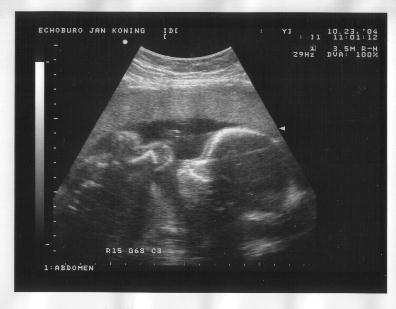

23 oktober 2004

Links: Zijaanzicht, waarbij het voorovergebogen ligt. Ruggewervel goed te zien